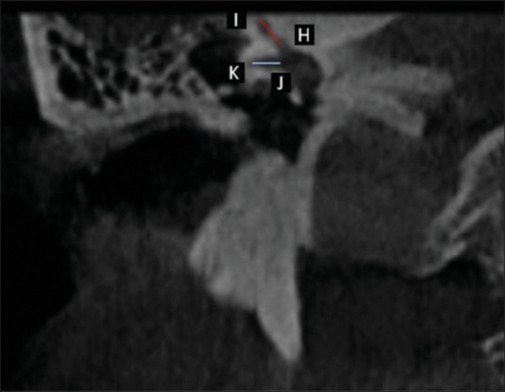

Introduction: The tympanic cavity contains three tiny bones, the malleus, incus, and stapes, which have a fundamental role in the transmission of sound. Recent research emphasizes the use of CBCT for the anatomic study of the temporal bone. The information about middle ear anatomy on CBCT scans is meager; hence, this retrospective study was conducted to identify and determine the various morphometrical parameters of the malleus using CBCT which can be helpful during reconstructive procedures for the otologic surgeon.

Materials and methods: The retrospective study was performed on 200 subjects (101 M and 99 F) in the Department of Oral and Maxillofacial Radiology. CBCT images of 200 subjects were studied in all planes to identify ossicular chain and the malleus to investigate the morphometric parameters in Indian Subjects.

Result: The average of morphometric parameters shows that the mean length of the malleus is 7.2 mm, the mean width of the head of the malleus is 3.02 mm, length of superior semicircular canal is 4.90 mm, and length of external auditory canal is 19.15 mm in Navi Mumbai population.